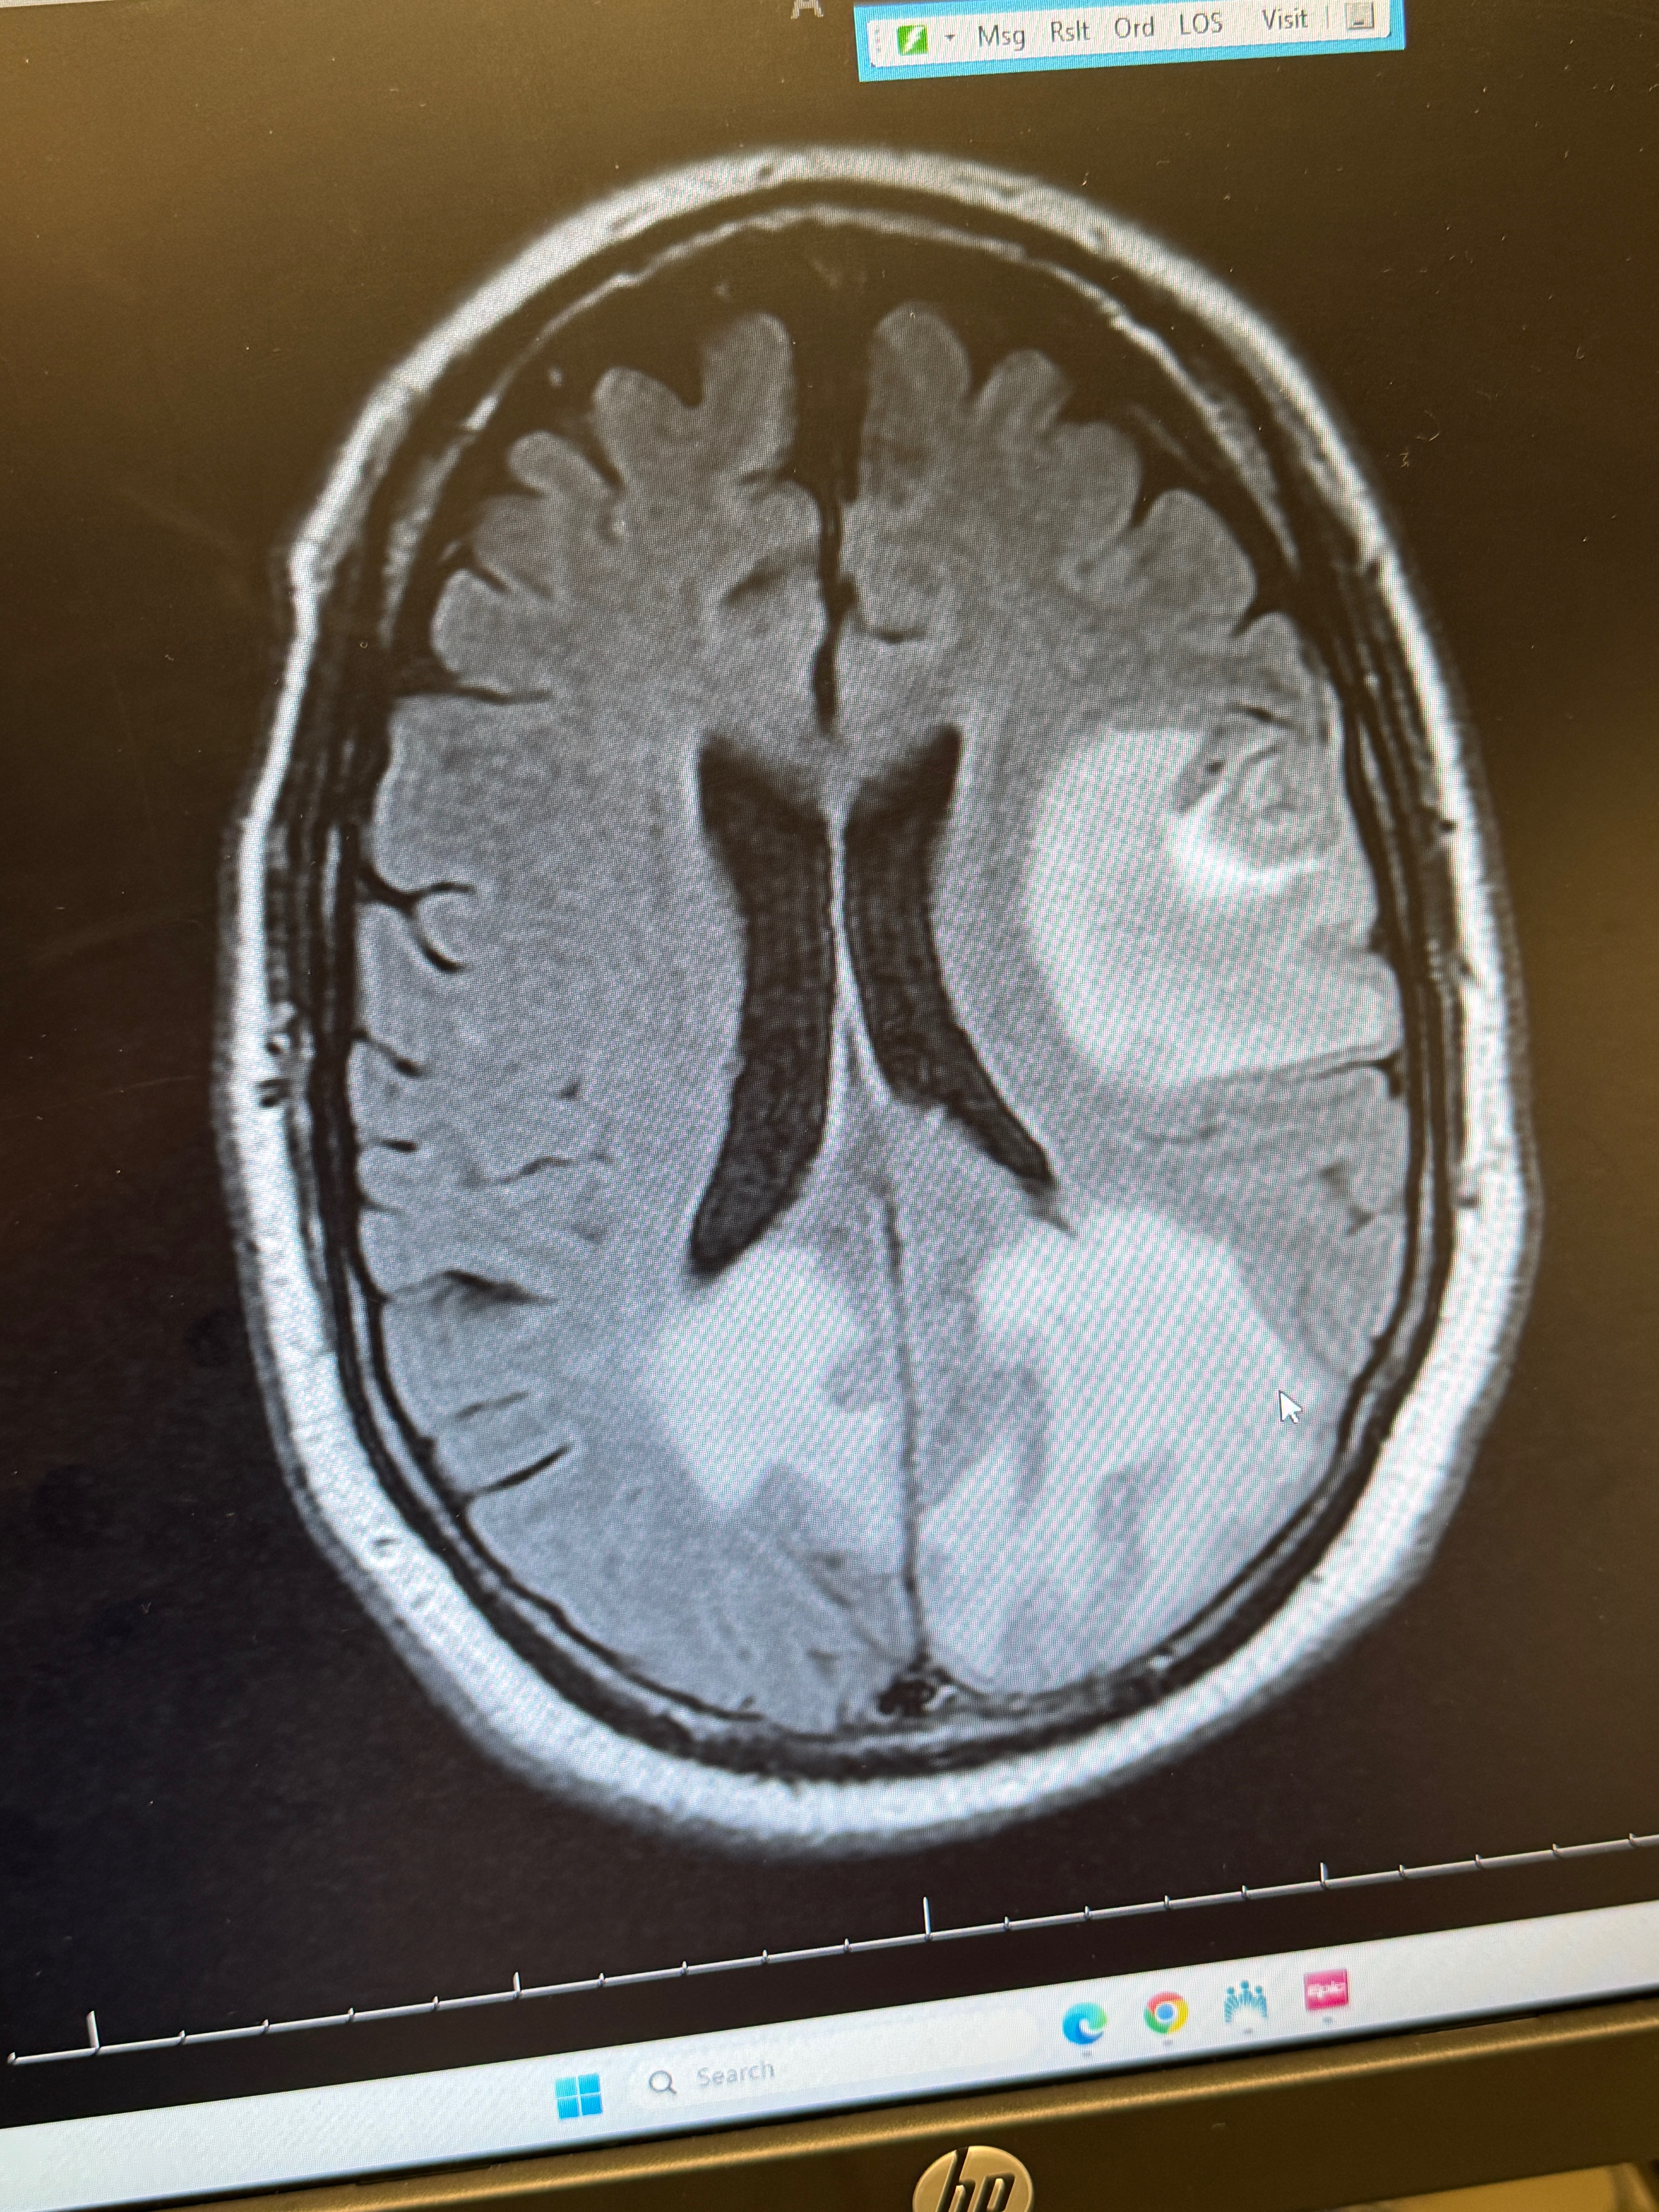

As many of you already know on August 18th, I was diagnosed with a highly aggressive and advanced form of brain cancer. After complaints of confusion and aphasia an MRI revealed multiple tumors, some quite large throughout my brain, and there was massive swelling. My blood sugars were way too high. My doctor sent me to the emergency room, where they told me the terrible new and admitted me immediately.

On September 15th my treatments began. They sent targeted radiation directly to the brain tumors, and I received my first chemotherapy infusion. In the days that followed my mind and body deteriorated into disability levels. I had extreme confusion and fatigue, painful mouth sores and swelling of my feet and legs. My recovery time has been more than 10 days to get to this point and I am still not 100% This was round one of ten. Nine more chemo infusions, the next one will be this Friday October 10th. I expect next week, and all the weeks following these treatments will be difficult.